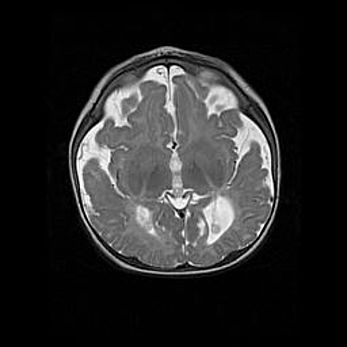

Множественные кисты обоих полушарий головного мозга, наибольшая из них в правой затылочной области. Ассиметричная атрофическая гидроцефалия.

Возраст: 7 месяцев

Вес: 5660 г

Пол: мужской

Окружность головы: 41,5 см

Срок гестации: 28-29 недель

Кисты головного мозга развиваются в результате многоочаговых некрозов вещества мозга и возникают вследствие перенесенной перинатальной инфекции, менингитов, энцефалитов, асфиксии, родовой травмы, расстройств мозгового кровообращения различного генеза. Образованию кист в веществе головного мозга плодов и новорожденных способствуют такие факторы, как высокое содержание в нем воды, недостаточная (или отсутствие) миелинизация и слабая астроглиальная реакция на повреждение.

Кисты могут сочетаться с гидроцефалией и другими поражениями головного мозга.